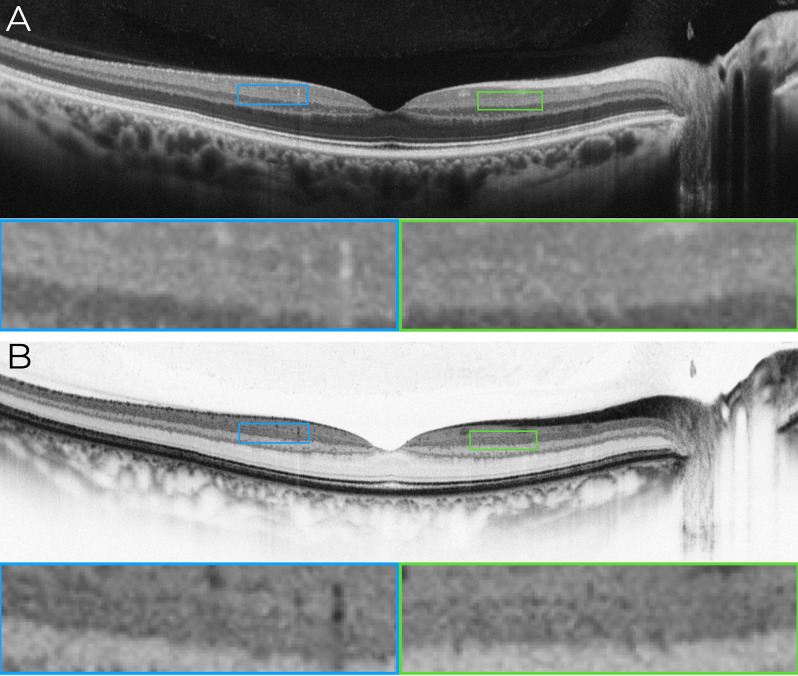

Methods: This retrospective, cross-sectional image analysis study included three healthy individuals who underwent macular OCT imaging. Two subjects were imaged with SD-OCT devices (Nidek RS3000 Advance and Zeiss Cirrus 6000), while one subject was imaged with a swept-source OCT (SS-OCT) device (Topcon Triton DRI). High-density B-scans (1024 A-scans per B-scan) with 120 repetitions for noise reduction were analyzed in both standard and inverted grayscale display modes. The impact of scan size (12 mm, 6 mm, and 3 mm) on IPL visualization was also evaluated.

Results: In conventional grayscale, IPL stratification was indistinct. However, inverted grayscale revealed five IPL sub-bands in all cases, particularly in the parafoveal region where the IPL is thicker. Hyperreflective dots near IPL-1, likely representing the superficial capillary plexus, were also identified. The 3-mm scan protocol provided superior sub-layer differentiation compared to 12-mm scans. However, SS-OCT images did not allow for the distinction of the five IPL strata.